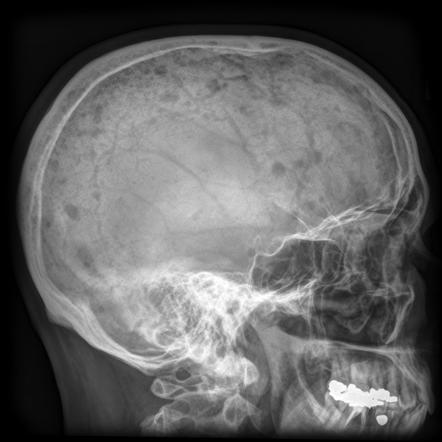

Рентгенологическая картина

Рентгеновская картина характеризуется большой вариабильностью. На типическом рентгеновском снимке определяются множественные очаги костной деструкции. Густые ограниченные деструктивные очаги сливаются с менее ограниченными и слабо выраженными просветлениями. Чередование остеолиза с пятнистыми сгущениями костной структуры создают своеобразную рентгенологическую картину множественной миеломы.

Фото множественной миеломы ребра на рентгенограмме

В стадии полного развития заболевания довольно часто выражена особая псевдокистозная структура, в особенности на черепе, ребрах, крыле подвздошной кости и позвонках.

В дальнейшей стадии развития множественной миеломы скелет на рентгеновском снимке может иметь вид растекшихся пчелиных сот. В поздних стадиях возникают выраженная атрофия всего скелета, патологические переломы с последующей остеобластической реакцией.

Рентгенологическая симптоматология солитарной миеломы проявляется ограниченным остеопорозом с ясными правильными контурами, очаговым лизисом, локализованным только на одной кости. Рентгеновские данные вначале могут иногда симулировать кариозный очаг.